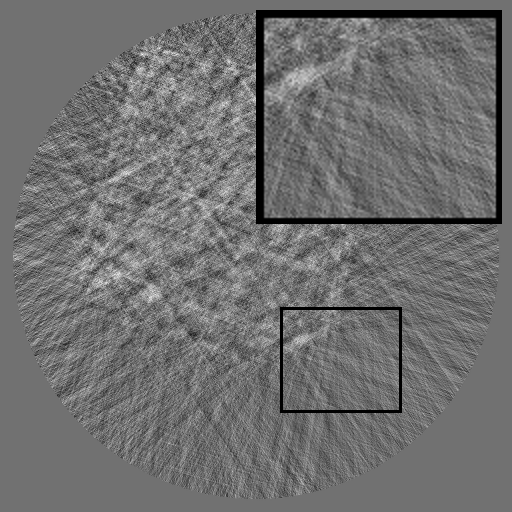

As shown in Fig 1, HiSin builds upon RePaint (Lugmayr et al., 2022) as its default backbone and restructures the inference process into a three-stage resolution-guided pipeline. The sinogram is first denoised at low resolution to establish global structure, then refined at mid resolution, and finally completed at full resolution through patch-wise inference. At each stage, the upsampled output from the previous resolution is fused with the current input before denoising, ensuring hierarchical guidance across scales. This hierarchical design avoids full-frame activation and substantially reduces memory usage while preserving long-range consistency. To further improve efficiency under the structural characteristics of sinograms, HiSin introduces two inference-time modules: (1) frequency-aware patch skipping, which exploits the spectral sparsity of background regions to bypass redundant computation, and (2) structure-adaptive step allocation, which leverages local structural heterogeneity to adjust denoising depth per patch.

Refer to caption

Figure 1: Overview of HiSin. The left illustrates the three-stage resolution-guided pipeline: low resolution followed by mid and high resolutions in a progressive refinement scheme, with the final stage performed patch-wise for detail recovery. At each stage, the upsampled output from the previous resolution is fused with the current input before denoising. The right zooms into the high-resolution stage, where two modules are applied: frequency-aware patch skipping (bypassing low-information patches) and structure-adaptive step allocation (assigning variable denoising steps by patch complexity).